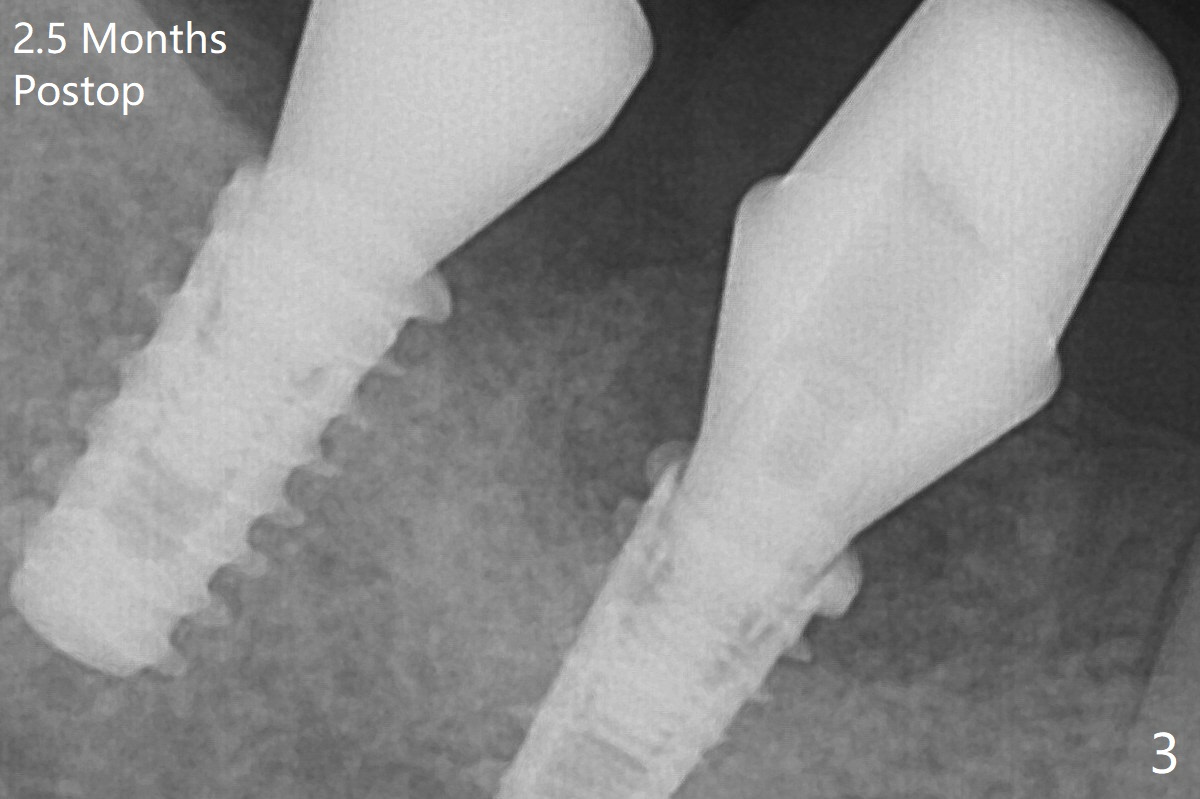

Note bone growth, especially at #30, 2.5 and 4 months postop (Fig.3,4). In fact the abutments are incompletely seated. The crown of #30 is loose with foul smell 2 years 8 months post cementation. It is painful to reinsert the crown/abutment after proximal reduction. A healing abutment is placed (Fig.5). When the incompletely seated abutment at #31 is removed, there is also smell. After separation from the crown, the abutment of #31 returns to the site with change in insertion position, while a smaller abutment has to be used at #30 (Fig.6) due to use of the small healing abutment earlier (Fig.5). A good piece of news is the presence of the bone between the implants (Fig.5,6 *), which contributes to interimplant papilla.